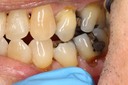

Kyle Chock#14 pre-op

Kyle Chock #14 caries removal

Kyle Chock #14 prep

Kyle Chock #14 finish